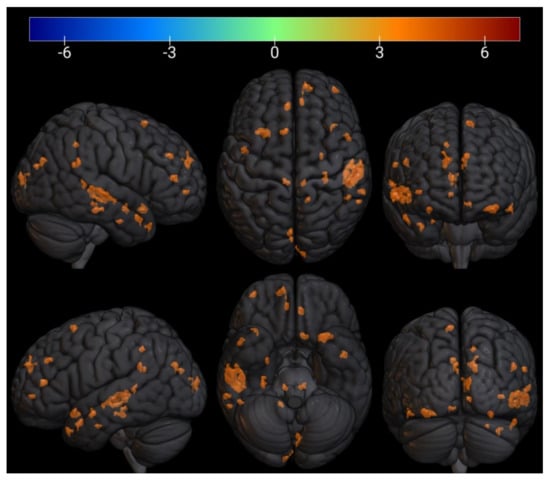

3.3. FMRI Analysis

| № Cluster | N Active Voxels in Cluster | Anatomical ROI | N Active Voxels in ROI | Peak MNI-Coordinates, mm | Peak T-Value | Peak p-Value | ||

|---|---|---|---|---|---|---|---|---|

| X | Y | Z | ||||||

| 1 | 34 | TP r (Temporal Pole) | 34 | 54 | 10 | −24 | 5.4 | 0.0002 |

| 2 | 9 | aPaHC r (Parahippocampal Gyrus) | 1 | 28 | −6 | −28 | 5.8 | 0.0001 |

| Hippocampus r | 8 | |||||||

| 3 | 11 | pPaHC r (Parahippocampal Gyrus) | 11 | 30 | −30 | −18 | 7.2 | 2.65 × 10−5 |

| 4 | 36 | IC l (Insular Cortex) | 6 | −34 | 16 | −16 | 5.7 | 0.0001 |

| FOrb l (Frontal Orbital Cortex) | 30 | |||||||

| 5 | 4 | TP r (Temporal Pole) | 4 | 40 | 16 | −20 | 4.8 | 0.0005 |

| 6 | 3 | PP l (Planum Polare) | 3 | −46 | 0 | −16 | 4.4 | 0.0008 |

| 7 | 6 | Brainstem | 6 | −8 | −32 | −12 | 5.5 | 0.0002 |

| 8 | 173 | pSTG r (Superior Temporal Gyrus) | 88 | 60 | −20 | −4 | 6.5 | 5.26 × 10−5 |

| pMTG r (Middle Temporal Gyrus) | 85 | |||||||

| 9 | 7 | Thalamus r | 1 | 12 | −32 | −4 | 6.6 | 5.25 × 10−5 |

| Brainstem | 6 | |||||||

| 10 | 10 | FP r (Frontal Pole) | 10 | 38 | 56 | −2 | 5.1 | 0.0003 |

| 11 | 11 | toMTG r (Middle Temporal Gyrus) | 5 | 62 | −40 | 4 | 5.3 | 0.0003 |

| pSMG r (Supramarginal Gyrus) | 6 | |||||||

| 12 | 10 | OP r (Occipital Pole) | 10 | 10 | −98 | 14 | 5.5 | 0.0002 |

| 13 | 10 | PaCiG l (Paracingulate Gyrus) | 8 | −14 | 46 | 6 | 4.9 | 0.0004 |

| AC (Cingulate Gyrus) | 2 | |||||||

| 14 | 3 | ICC l (Intracalcarine Cortex) | 3 | −16 | −74 | 10 | 4.9 | 0.0004 |

| 15 | 16 | PaCiG r (Paracingulate Gyrus) | 7 | 10 | 42 | 12 | 4.8 | 0.0005 |

| AC (Cingulate Gyrus) | 9 | |||||||

| 16 | 6 | OP r (Occipital Pole) | 6 | 6 | −94 | 14 | 5 | 0.0004 |

| 17 | 28 | FP r (Frontal Pole) | 28 | 28 | 52 | 20 | 5 | 0.0004 |

| 18 | 17 | AG r (Angular Gyrus) | 17 | 62 | −48 | 24 | 4.4 | 0.0008 |

| 19 | 14 | PaCiG l (Paracingulate Gyrus) | 14 | −6 | 40 | 32 | 5.9 | 0.0001 |

| 20 | 4 | Precuneous (Precuneous Cortex) | 4 | 16 | −46 | 42 | 5.1 | 0.0003 |

| 21 | 7 | SFG l (Superior Frontal Gyrus) | 7 | −10 | 16 | 60 | 4.9 | 0.0004 |

| 22 | 5 | FOrb r (Frontal Orbital Cortex) | 5 | 26 | 30 | −14 | −5.1 | 0.0003 |

| 23 | 7 | PreCG l (Precentral Gyrus) | 7 | −6 | −26 | 58 | −5.8 | 0.0001 |